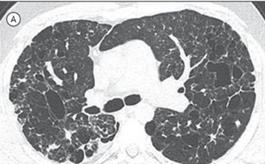

A imagem tomográfica mais frequentemente associada à linfangioleiomiomatose é a seguinte: